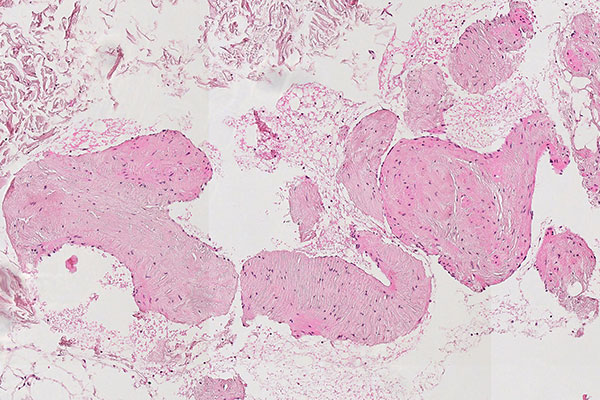

Histopathological section; hematoxylin & eosin (HE) stain, 90x magnification of the punch cylinder. Punch cylinder showing parts of venous malformation with densely packed, irregularly configured large-caliber venous vessel parts. These do not appear tubular as in a normal mature vessel, but as if the vessels are "everted". The lumen looks solid and blood is all around the outside.

Histopathological section; hematoxylin & eosin stain (HE), 160x magnification of the punch cylinder. Here it is clear to see that the irregular, blood-filled spaces of the venous malformation are not solid, but are "voids" partially filled with erythrocytes. The endothelial lining corresponds to the outer border of the visible lesion.

Purely histopathological diagnosis of a lesion as a venous malformation under the microscope is hardly possible without corresponding clinical information and appropriate clinical referral. Nevertheless, there is good evidence that will characterize a venous malformation based on immunohistology and morphology. The venous malformation is a spongy, blood-filled lesion without any real solid parts, similar to a Swiss cheese with a lot of air (air holes = blood-filled cavities; cheese = dysplastic, venous wall structures). Thus, the actual dysplastic vein walls make up only a fraction of the volume in the overall blood-filled lesion and usually appear irregularly branched like a foxhole rather than tubular.

Immunohistochemical staining with CD31 (blood vessel endothelium) lining the lesion, and the irregular, sometimes patchy, asymmetric surrounding of smooth muscle cells (SMA stain) as well as evidence of atypical collagen and elastic fibers (EvG stain) distributed in the venous vessel wall make the diagnosis highly probable. Venous malformations show little proliferative activity (MIB-1). The histopathologically very similar-looking lymphatic malformation can be well differentiated by D2-40 (podoplanin) staining, which specifically stains only lymphatic vessel endothelia.